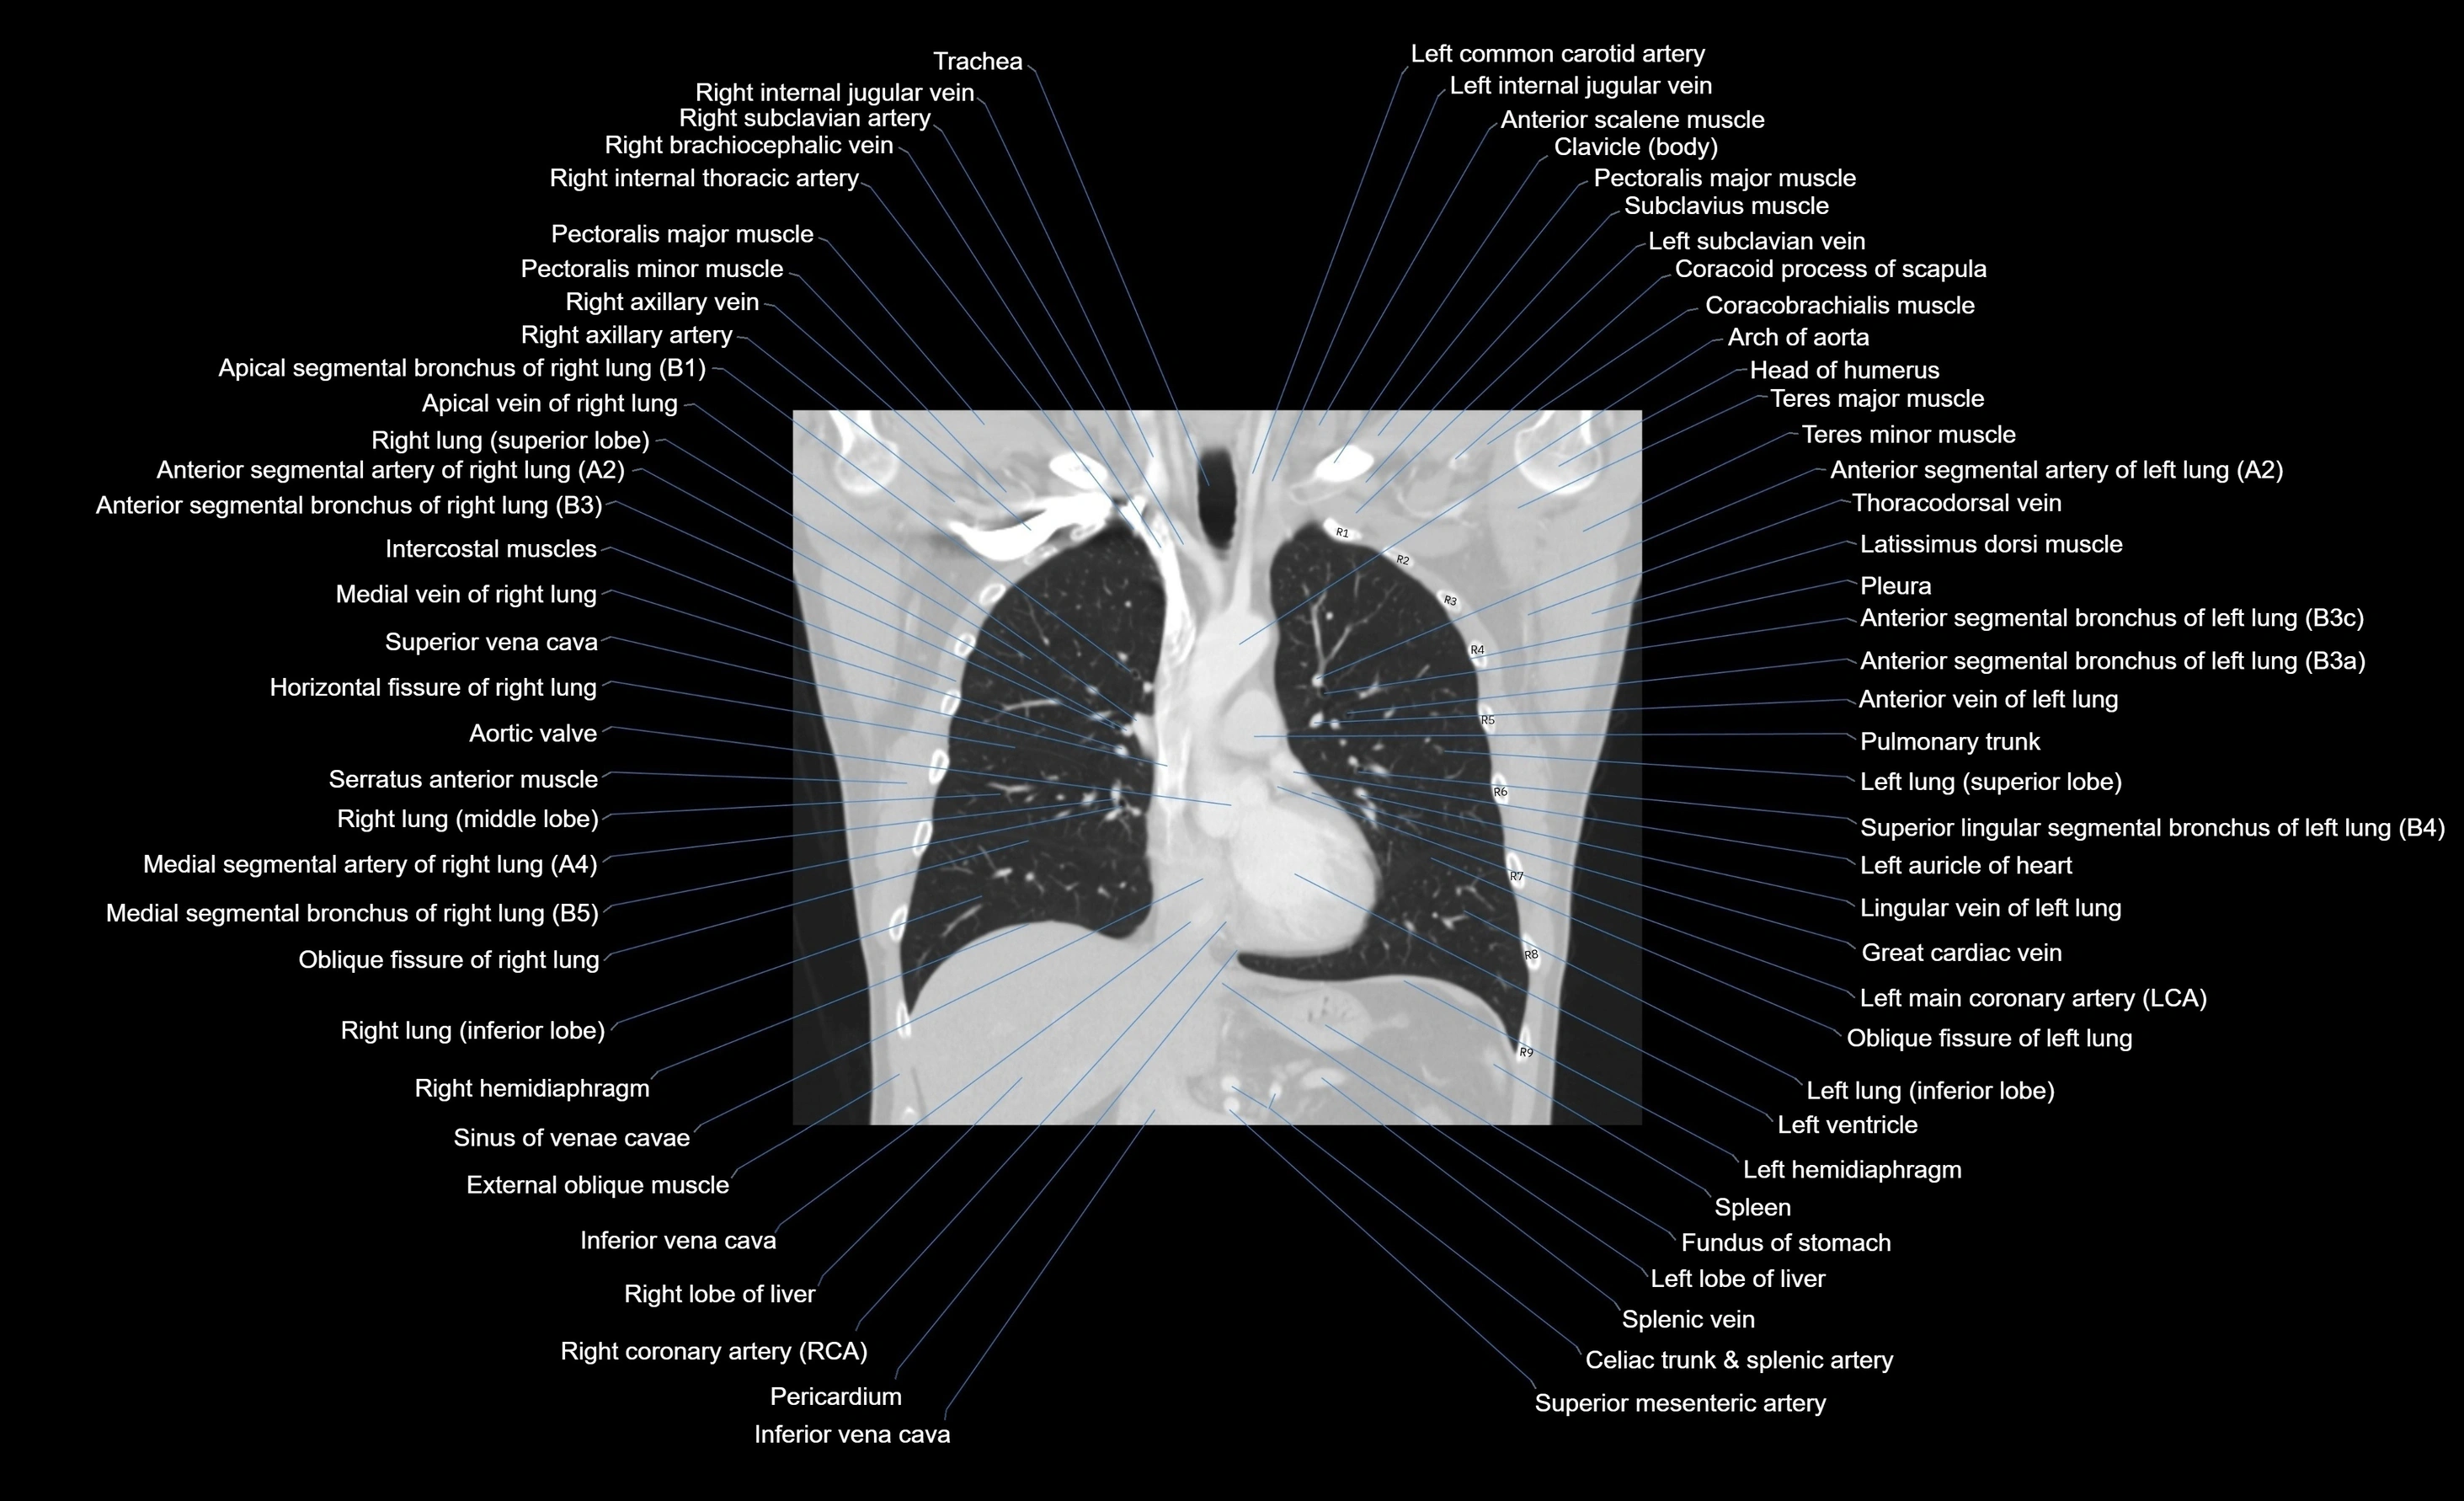

- T (Thoracic spine)